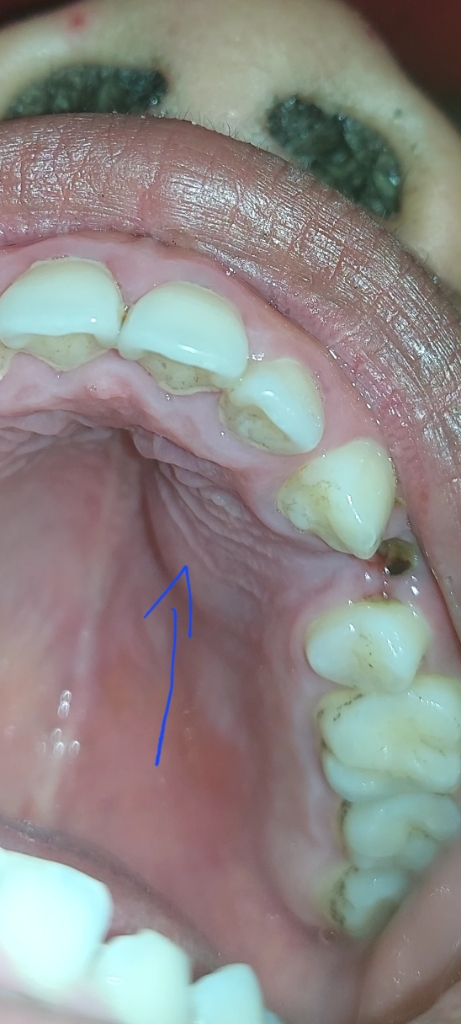

Đau răng và bị sưng trong khoang miệng .đau buốt khó khủ

Chỗ bị sưng là viêm lợi đúng không ạ